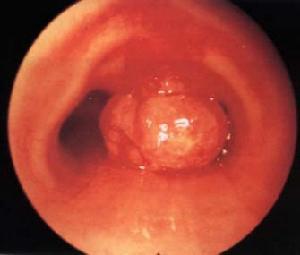

气管肿瘤有良性肿瘤和恶性肿瘤两大类。儿童期的气管肿瘤绝大部分(90%)为良性,成人者恶性占多数。本病不论良性或恶性均应手术治疗。良性肿瘤切除后,完全痊愈,恶性肿瘤若能及时彻底切除,亦能获得良好的疗效。